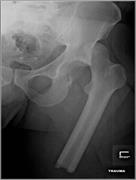

The irreducible floating hip: a unique presentation of a rare injury

Nathan C. Tiedeken and others

Journal of Surgical Case Reports, Volume 2013, Issue 10, October 2013, rjt075, https://doi.org/10.1093/jscr/rjt075